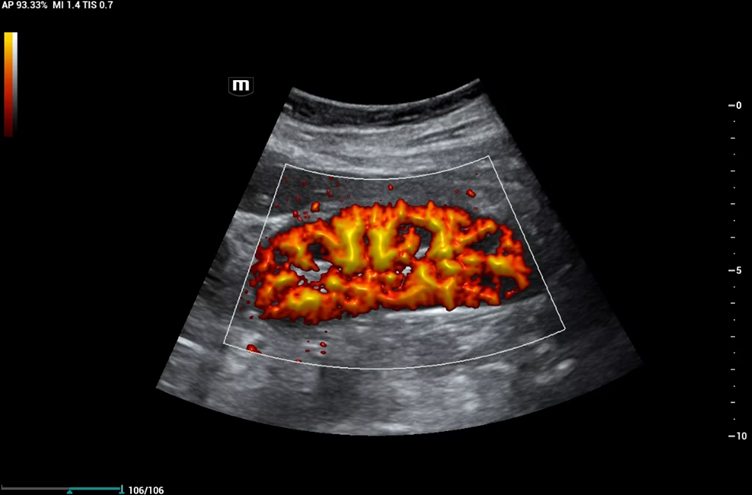

Power Doppler image showing renal perfusion

Power Doppler (PD) also known as Power Doppler Imaging (PDI) is very similar to Colour Doppler, except that it is non-directional. Therefore, Power Doppler is not typically used in echocardiography where direction of flow is key to assessing the heart.

Power Doppler offers increased sensitivity, making it easier to visualise small vessels and low-velocity blood flow. It detects the amount of movement rather than direction, so regions with more moving blood cells appear brighter on the image — and unlike other Doppler modes, it has no maximum velocity limit.

The disadvantage is that extra sensitivity means more flash artefact. If the probe or patient is moving, the motion will appear more strongly than with Colour Doppler.